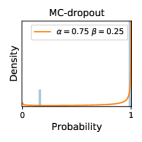

5.1 Distribution of Uncertainty Scores

Distribution of Uncertainty Scores Across Different Severity Levels As explained in Section 3, each uncertainty metric essentially defines an order/ranking among the data points. We conducted an analysis to better understand what data will be assigned high uncertainty under a particular uncertainty metric . Picking out the highest ranked data points (), we calculated the ratio of data points from each SL. Figure 4 summarizes the results as box plots for the Kaggle-DR and the Messidor-2 datasets; additional detailed statistics can be found in Table S.1 in the supplementary materials. From the plot and table, SL1 & SL2 examples account for a higher proportion among the top-ranked uncertain examples across the three ensemble methods. This finding matches our intuition that incipient disease examples (SL1 & SL2) are more likely to be considered uncertain by ensemble methods due to their ambiguity.

In contrast, the MC-dropout method showed the worst overall performance among the three, as it can be seen from the high ratios of SL0 examples among the uncertain negatives in Figure 4. The histograms in Figure 2 provides another perspective to look into the phenomenon, where a decent proportion of MC-dropout model’s predictions on SL0 inputs entailed low confidence (far from 0 or 1), which from another angle explained why MC-dropout was less specific in terms of lower FNP; many no-DR inputs (i.e. SL0) were erroneously assigned high uncertainty by MC-dropout models.

It is still an open question why the evaluated MC-dropout networks signaled relatively high uncertainty on SL0 & SL3 & SL4 data that are less likely to be ambiguous. We conjecture that much of the “uncertainty” indicated by disagreement among test-time dropout samples actually reflects the stochastic nature of dropout networks rather than the real decision uncertainty associated with the data. It is worth noting that the MC-dropout model we evaluated was not weak per se; they all achieved above Area Under Curve (AUC) scores on test sets. The weakness of individual test-time samples (which explains their low-confidence predictions on SL0 & SL3 & SL4) might have been hidden when they are aggregated into an ensemble—a well-known advantage of ensemble learning. Our results suggested that the uncertainty information given by implicit ensemble methods such as MC-dropout and TTA might not be as reliable as that from explicit ensemble approaches (e.g., stacking ensembles). Similar findings on MC-dropout can be found in some previous papers [1].